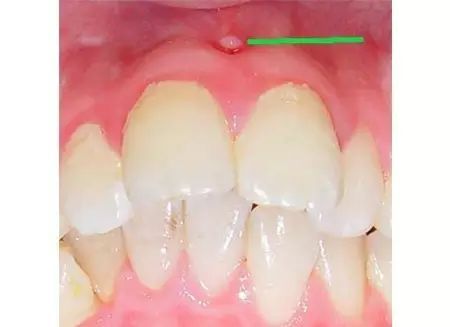

第五步:急性根尖周炎

当您脸肿得睁不开眼睛时,您撑着眼睛说:“没什么大不了的,吃吃消炎药就好了。”

牙医却着急地说:“牙齿急性根尖周炎感染可能引起间隙感染,严重的会危及生命。此时,需要到正规牙科治疗患牙,配合药物治疗,必要时做脓肿切开引流术。”